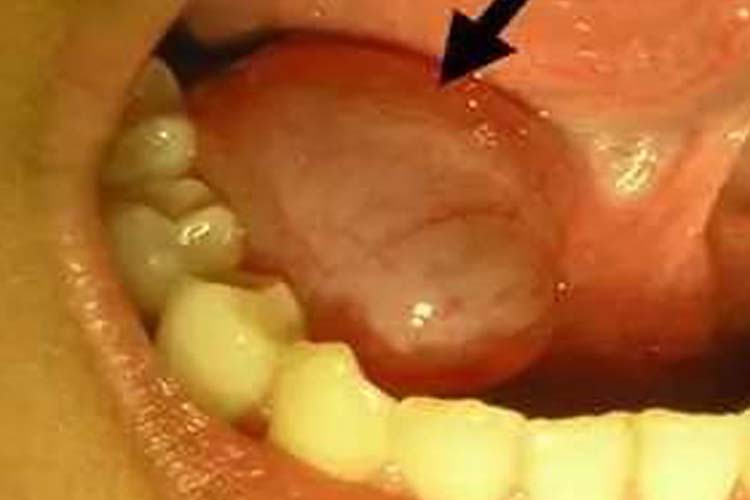

舌下腺导管开口处小肉芽

临床图片舌下腺囊肿为舌下腺导管堵塞,知道涎液潴留所形成的什舌囊肿.

br>舌头底下凸起的肉疙瘩,有可能是正常的舌下肉阜,舌下腺导管开口

舌下腺导管口发炎图片_有来医生